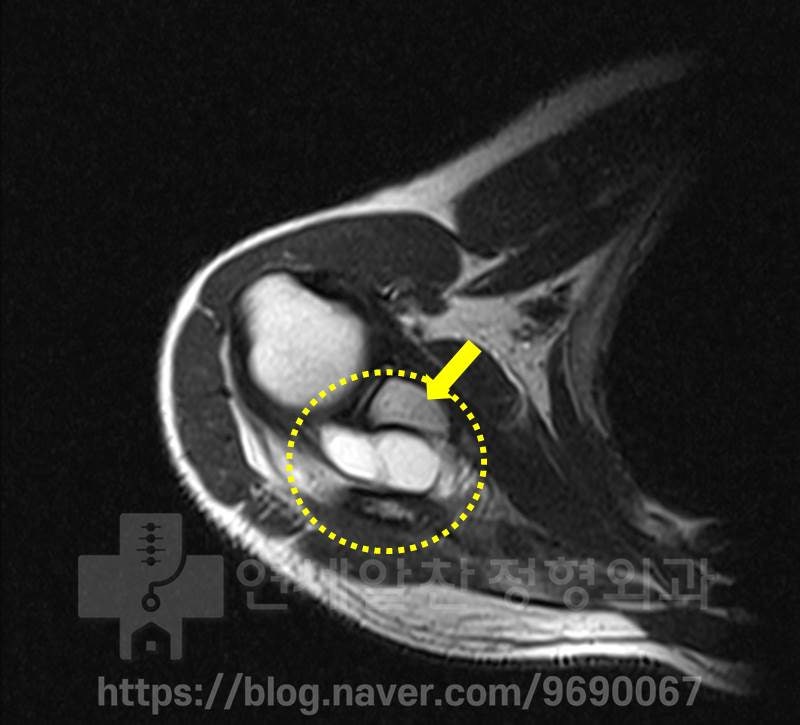

노란색 원형으로 표시된 부위의 하얀색 부위가 어깨 물혹입니다. 아주 커다란 어깨 물혹이 관찰됩니다. 하지만 관절와순의 손상은 관찰되지 않았습니다..

비슷한 위치로 다시한번 커다란 어깨물혹이 관찰되고 있으며 관절와순의 손상은 확인되지 않습니다.